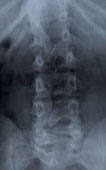

X-RAY of Damaged Spine